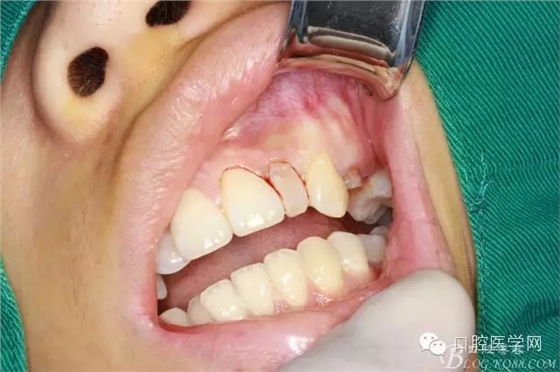

垂直切口

水平切口

翻全厚瓣(-)

翻全厚瓣(二)

翻全厚瓣后暴露骨面